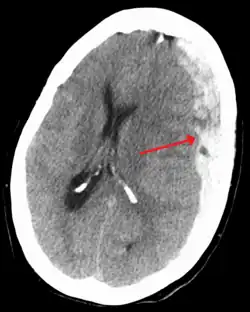

Diagnosen stilles typisk ved CT-scanning af hovedet. Alternativt kan MR-scanning bruges. SDHer opstår oftest over frontal- eller temporallapperne.[3][8] De kan også forekomme i kraniets fossa posterior, ved falx cerebri og tentorium cerebelli.[3]

På en CT-skanning kan et SDH ses som en linseformet bramme med den konkave side mod hjernen. I den akutte fase ses det friske blod som klart hvidt på billederne, men senere vil den gå over i lysegrå i takt med at blodet reabsorberes. Til forskel for epidurale blødninger er SDHer ikke afgrænset af kraniets suturer og vil derfor brede sig over en større del af hjernens overflade. På hjernens overflade, umiddelbart under blødningen, kan der være hypodensitet (mørkfarvning) af hjernevævet, som tegn på iskæmi og medfølgende væskeansamling.